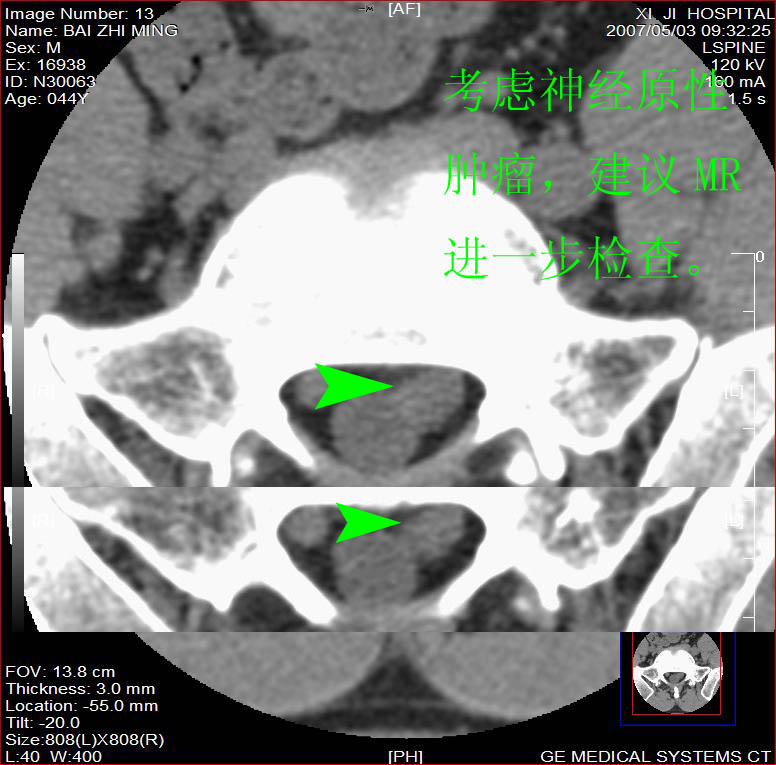

男,44岁,腰痛3月,加重3天。

同意2楼,左侧神经根增粗,欠规整,神经根炎或神经源性肿瘤可能,建议mri检查。

左侧神经根增大.并硬脊膜囊受压(1,神经根炎2神经根肿瘤)

左侧神经根增粗,欠规整,神经根炎或神经源性肿瘤可能,建议mri检查